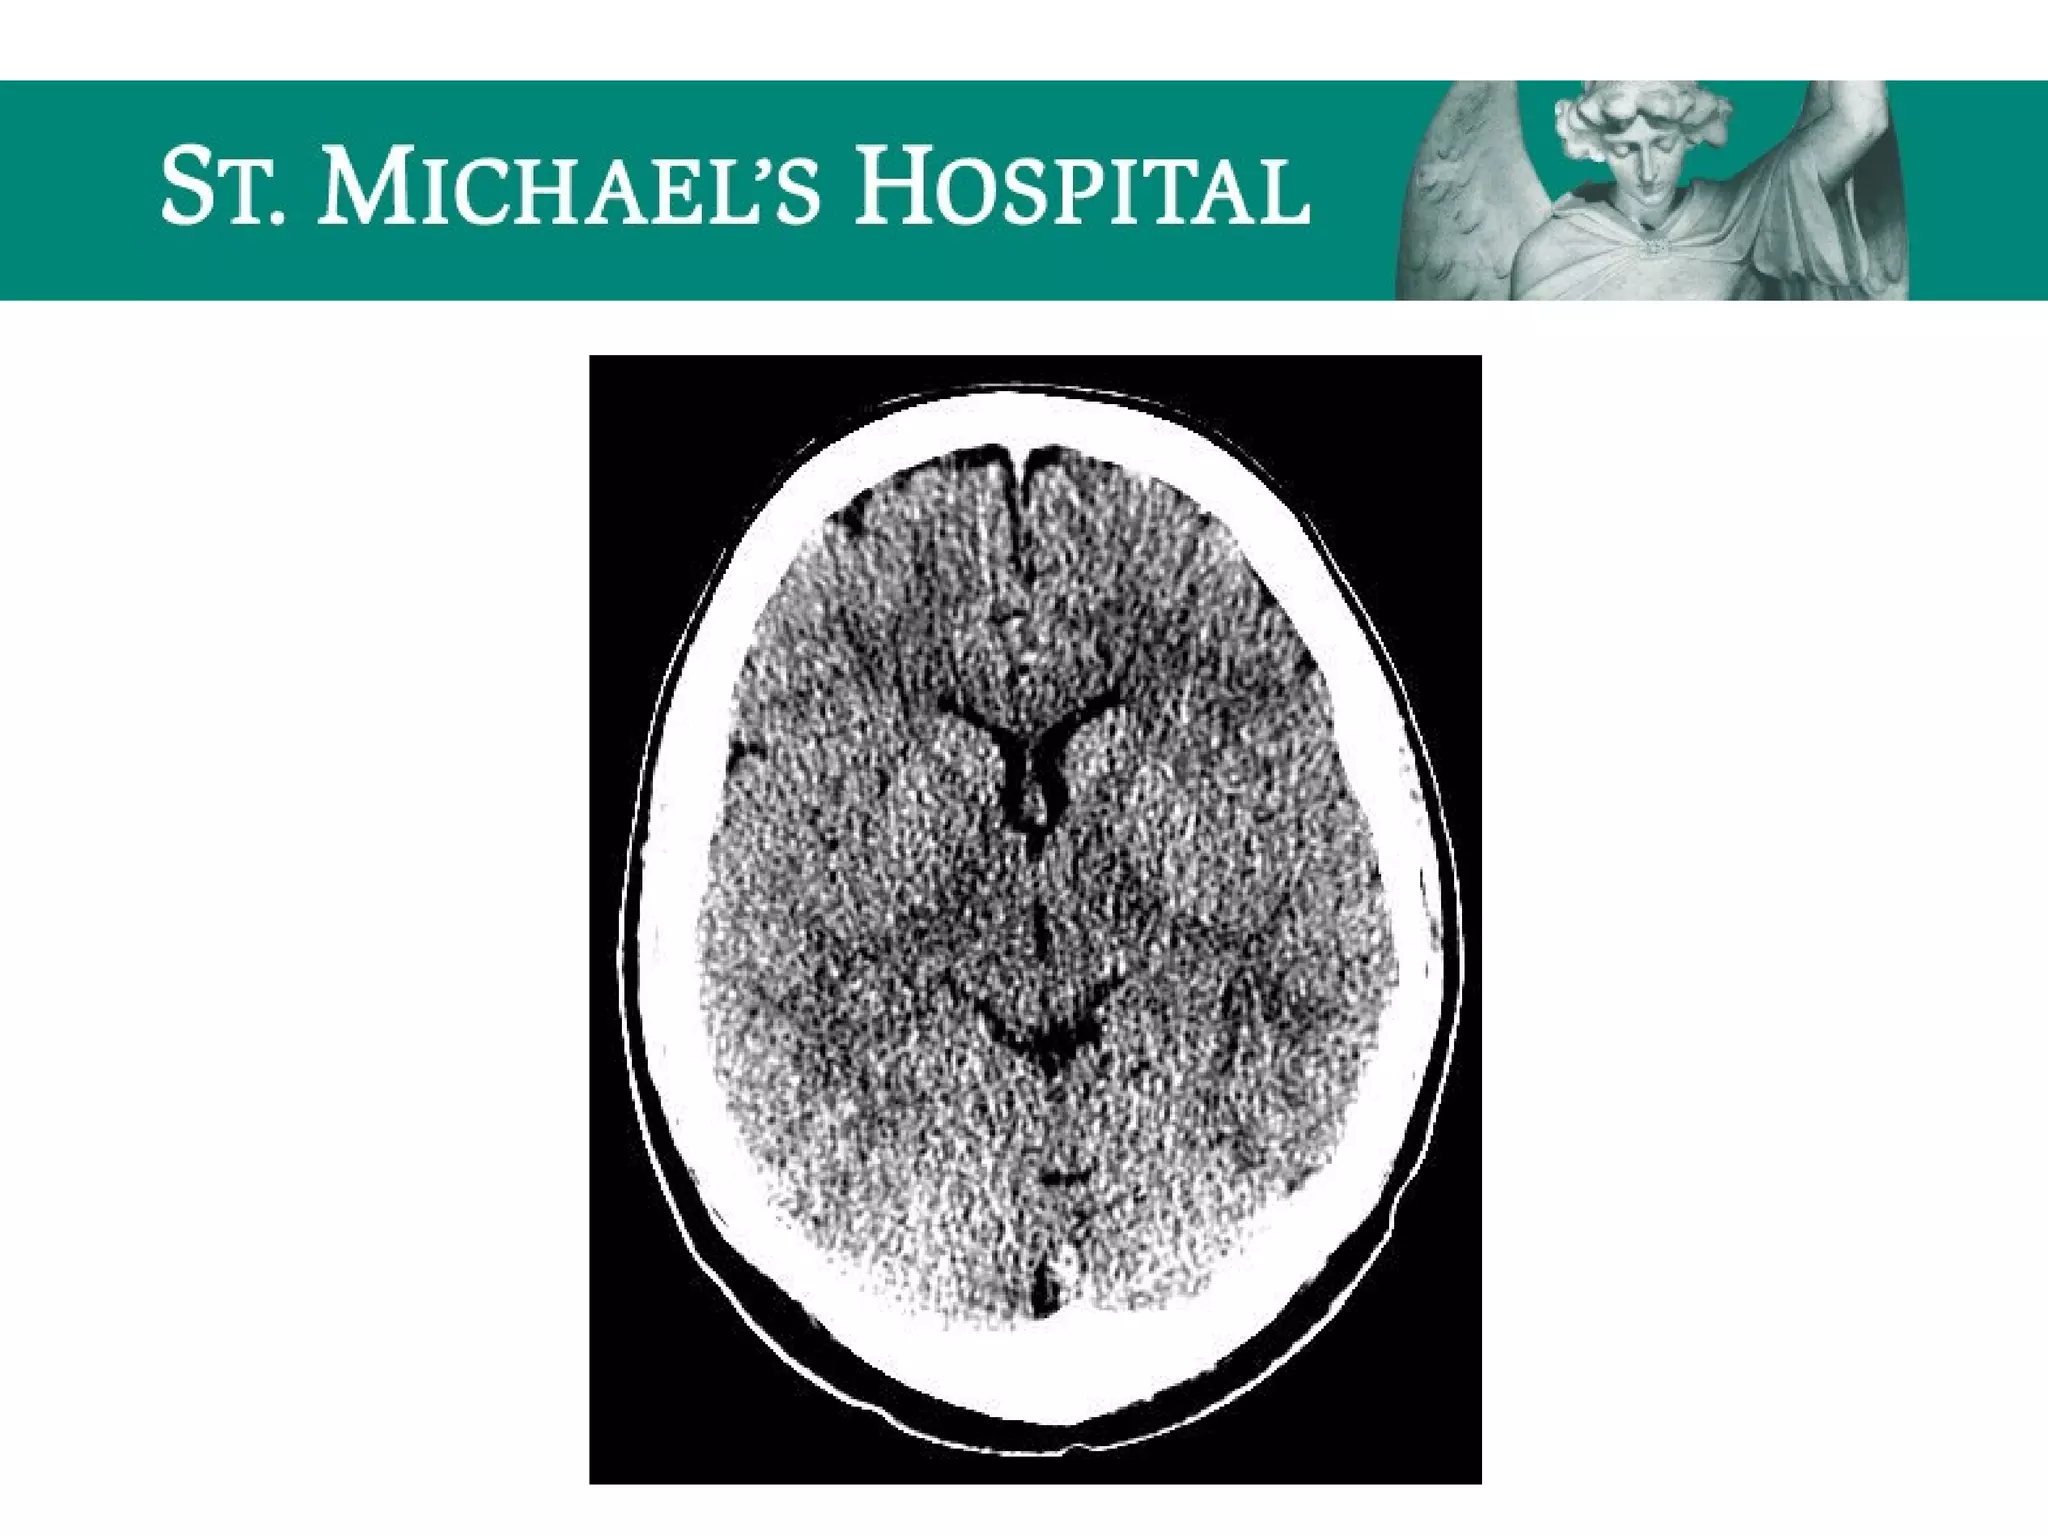

Global Cerebral Ischemia/Anoxic Brain

Injury

 Diffuse brain swelling/edema can result in:

 global loss of gray-white differentiation

 global sulcal/cisternal effacement

 pseudo-subarachnoid hemorrhage

 dense cerebellum

Global Cerebral Ischemia/AnoxicBrain Injury  Diffuse brain swelling/edema can result in:  global loss of gray-white differentiation  global sulcal/cisternal effacement  pseudo-subarachnoid hemorrhage  dense cerebellum